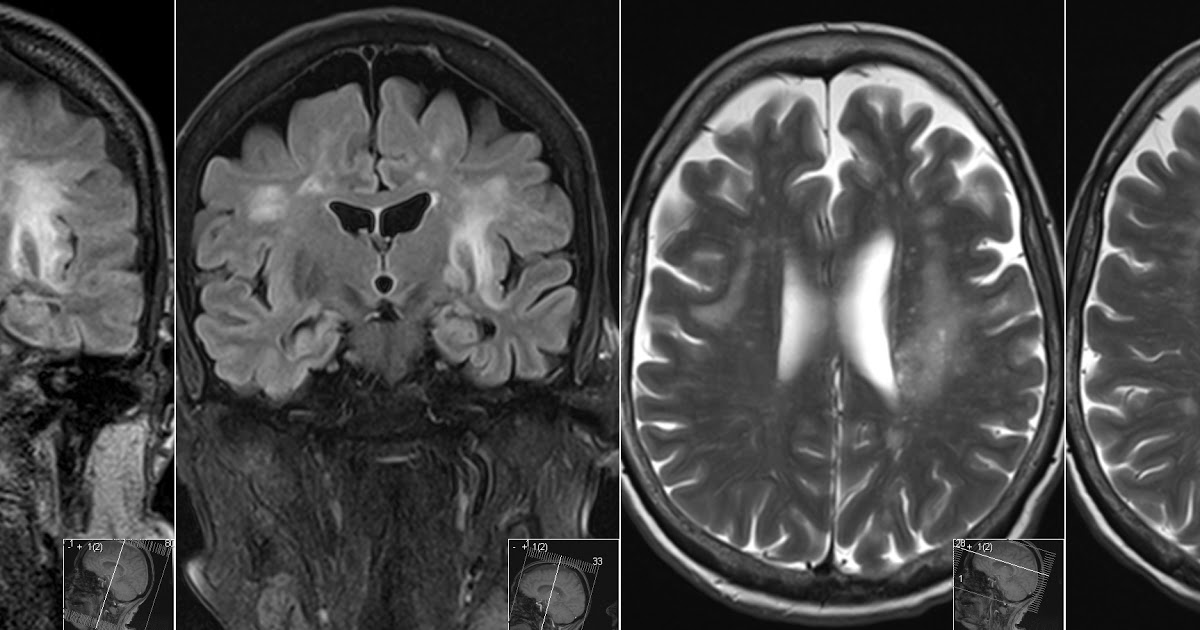

Warning Signs Of Progressive Multifocal LeukoencephalopathyProgressive multifocal leukoencephalopathy (PML), a type of demyelination, is a disease caused by the JC virus that occurs when the body is unable to fight against…March 11, 2019